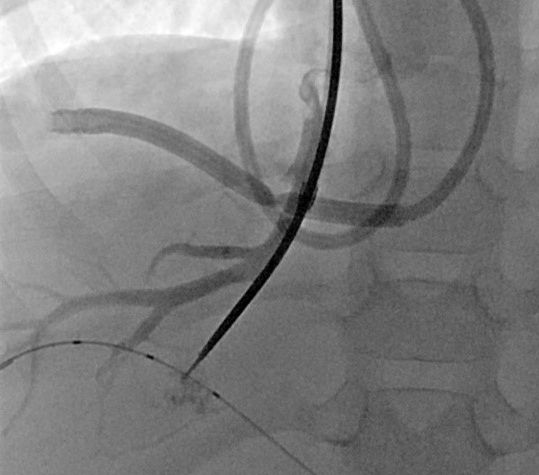

Ausgedehntes fokales Leberhämangiom eines Neugeborenen

Reifes Neugeborenes mit Hepatomegalie und Herzinsuffizienz. Das MRT der Leber (A) zeigte ein ausgedehntes kongenitales Hämangiom mit normalem Lebergewebe in den Randbereichen vor allem links. Deutlich gestaute Lebervenen (B) infolge der Rechtsherzbelastung. Die Kontrastmittelinjektion die Arteria hepatica dextra (C) zeigt mehrere arterielle Feeder mit rascher Parenchympassage. Nach interventionellem Verschluss mittels 3 Vascular Plugs und insgesamt 28 Volumen-Coils deutliche Reduktion des Shunt-Flusses im rechten Leberlappen mit noch verbleibenden Hämangiomanteilen links (D).